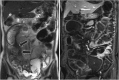

Intestinal stricture in Crohn's disease

Crohn's disease (CD) is a disease with chronic inflammation of unknown etiology involving any part of the gastrointestinal tract. The incidence and prevalence of CD are increasing recently in Asia. Half of the CD patients will have intestinal complications, such as strictures or fistulas, within 20 years after diagnosis. Twenty-five percentage of CD patients have had at least one small bowel stricture and 10% have had at least one colonic stricture and lead to significant complications. Most of these patients will require at least one surgery during their lifetime. Early diagnosis and evaluation with adequate managements for the patients can prevent disability and mortality of these patient. Here, we reviewed the current incidence of CD with stricture, the etiology of stricture, and how to diagnose and manage the stricture.